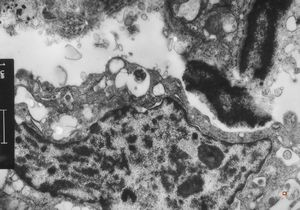

normal seromucinous salivary gland